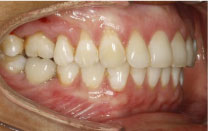

Two continuous power chains anchored on the micro screws were placed, in a criss-crossed fashion over the occlusal face of the molar applying 50 gr. of force measured with a PCE-LFG 10 dynamometer. The intrusion was done in an axial direction. Every 21 days the power chains were replaced by new ones and always set in position with composite (Figure 3).

Figure 3: Intrusion mechanism in piece 1.6. View Figure 3

In six months the tooth was intruded and for the following six months it was held in retention by replacing the power chain, in the same fashion, with 0.012" metallic ligatures.